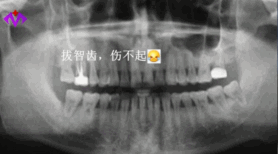

明明知道智齒就是口腔里的“定時(shí)炸彈”,極容易導(dǎo)致智齒冠周炎、損害鄰牙等問(wèn)題,卻因?yàn)榕绿邸⑴侣闊?、想省錢,非得等到問(wèn)題爆發(fā),才肯踏進(jìn)牙科的大門。

智齒長(zhǎng)的位置不同,拔除的收費(fèi)也不一樣。